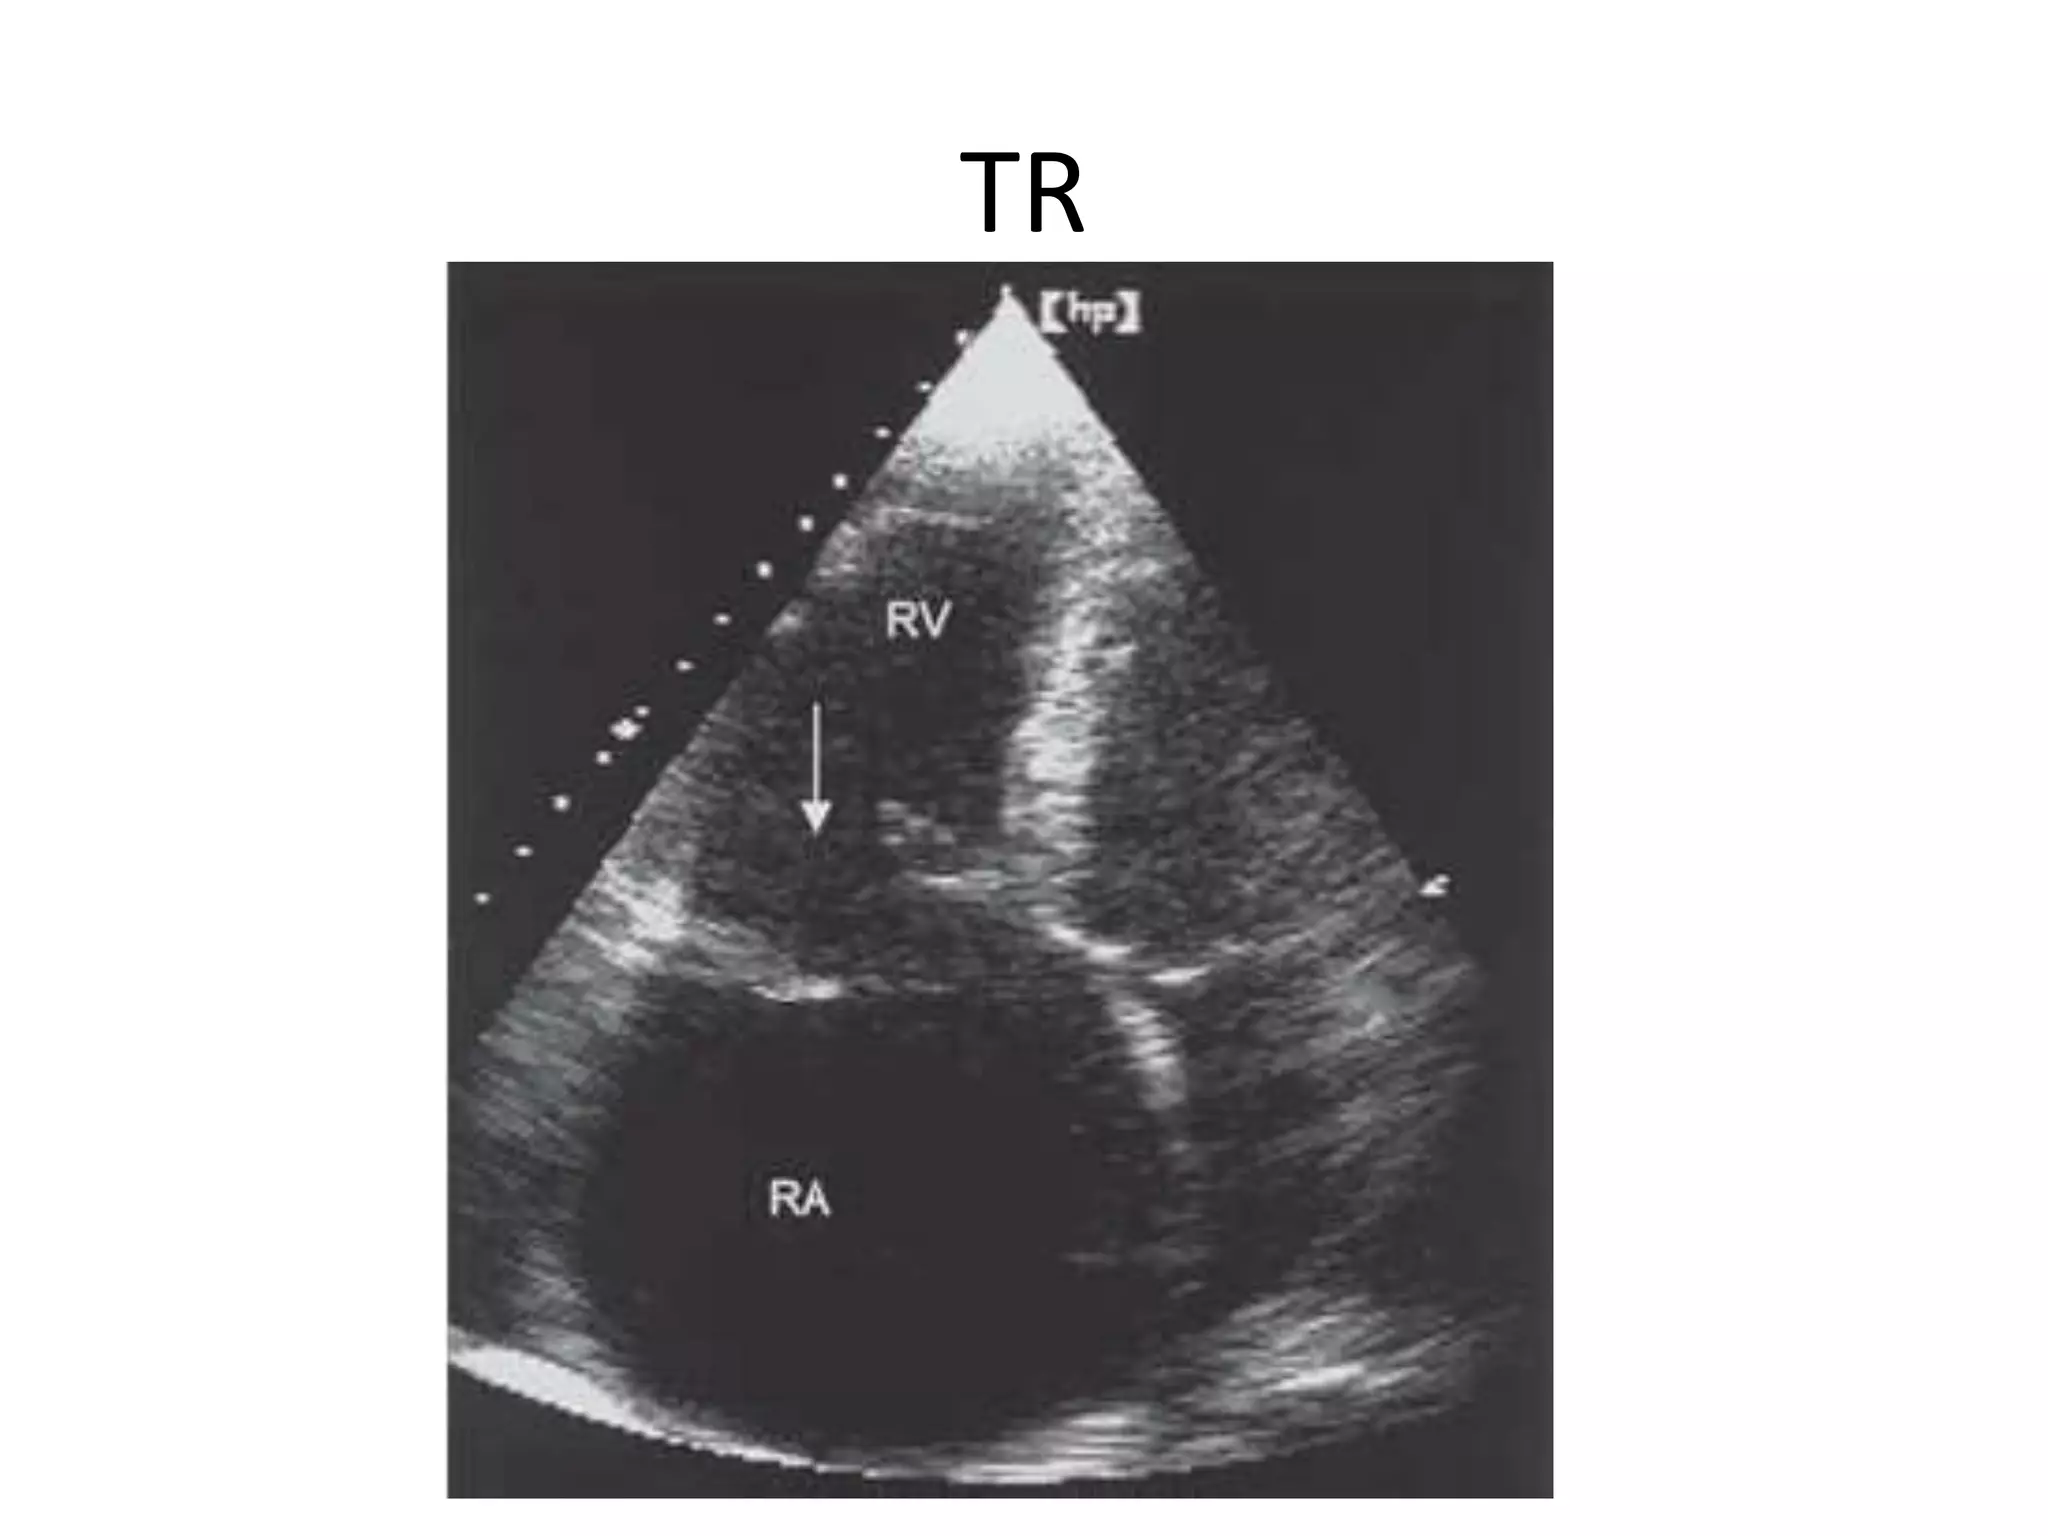

TR

• Doppler

– This is the best method to assess PA systolic pressure

using TR velocity (as described in Ch. 3), or short PA

acceleration time as a surrogate of PHT.